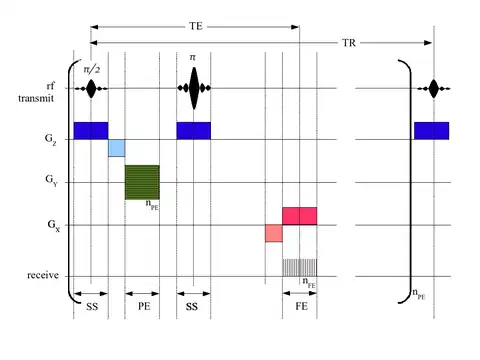

Each tissue returns to its equilibrium state after excitation by the independent relaxation processes of T1 (spin-lattice; that is, magnetization in the same direction as the static magnetic field) and T2 (spin-spin; transverse to the static magnetic field). To create a T1-weighted image, magnetization is allowed to recover before measuring the MR signal by changing the repetition time (TR). This image weighting is useful for assessing the cerebral cortex, identifying fatty tissue, characterizing focal liver lesions, and in general, obtaining morphological information, as well as for post-contrast imaging. To create a T2-weighted image, magnetization is allowed to decay before measuring the MR signal by changing the echo time (TE). This image weighting is useful for detecting edema and inflammation, revealing white matter lesions, and assessing zonal anatomy in the prostate and uterus.

A gradient echo sequence does not use a 180 degrees RF pulse to make the spins of particles coherent. Instead, it uses magnetic gradients to manipulate the spins, allowing the spins to dephase and rephase when required. After an excitation pulse, the spins are dephased, no signal is produced because the spins are not coherent. When the spins are rephased, they become coherent, and thus signal (or "echo") is generated to form images. Unlike spin echo, gradient echo does not need to wait for transverse magnetisation to decay completely before initiating another sequence, thus it requires very short repetition times (TR), and therefore to acquire images in a short time. After echo is formed, some transverse magnetisations remains. Manipulating gradients during this time will produce images with different contrast. There are three main methods of manipulating contrast at this stage, namely steady-state free-precession (SSFP) that does not spoil the remaining transverse magnetisation, but attempts to recover them (thus producing T2-weighted images); the sequence with spoiler gradient that averages the transverse magnetisations (thus producing mixed T1 and T2-weighted images), and RF spoiler that vary the phases of RF pulse to eliminates the transverse magnetisation, thus producing pure T1-weighted images.[39]